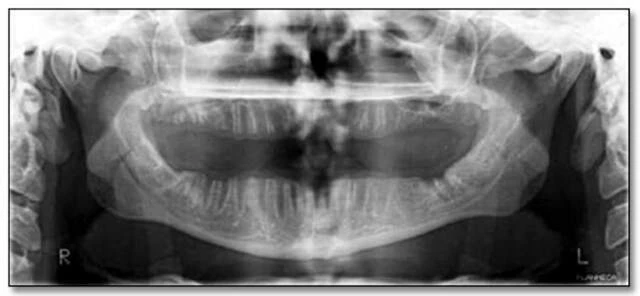

Hình 34a

Hình 34b: Hinh ảnh bị phơi sáng quá mức (Liều bức xạ cao)

thể hiện rõ ràng sự xuất hiện của một vùng bức xạ gây ra sự mở rộng và mỏng đi của phần xương bên dưới của hàm phải – những đặc điểm không thể hiện rõ trên bản gốc.

Hai hình ảnh trên cho thấy việc chụp với liều tia quá cao có thể dẫn đến các thất bại trong việc phát hiện các đặc điểm bệnh lý.

Hình ảnh thể hiện mức độ tiếp xúc quá mức có thể dẫn đến việc không phát hiện được các đặc điểm bệnh lý. Hình 34a là phiên bản nâng cao kỹ thuật số của bức ảnh 34b. Có thể thấy Hình 34b bị phơi sáng quá mức khi chụp, thể hiện rõ ràng sự xuất hiện của một vùng bức xạ gây ra sự mở rộng và mỏng đi của phần xương bên dưới của hàm phải – những đặc điểm không thể hiện rõ trên bản gốc.